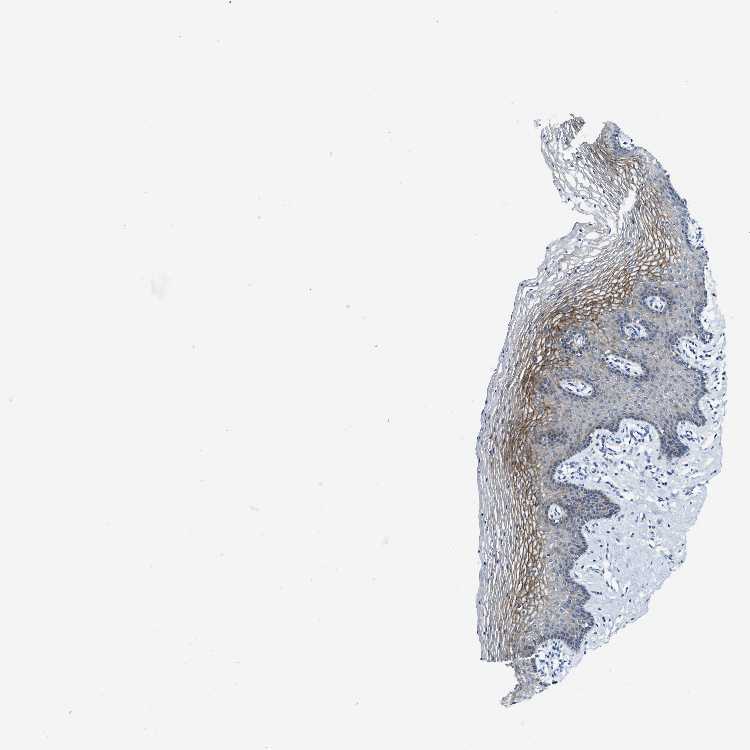

TISSUE PRIMARY DATA VAGINA Show tissue menu

VAGINA - Antibody stainingi

Antibody staining in the annotated cell types in the current human tissue is reported as not detected, low, medium, or high, based on conventional immunohistochemistry profiling in selected tissues. This score is based on the combination of the staining intensity and fraction of stained cells.

Each image is clickable and will lead to virtual microscopy that enables deeper exploration of all samples and also displays staining intensity scores, fraction scores and subcellular localization as well as patient and tissue information for each sample.

Antibody HPA018331

Squamous epithelial cells Medium